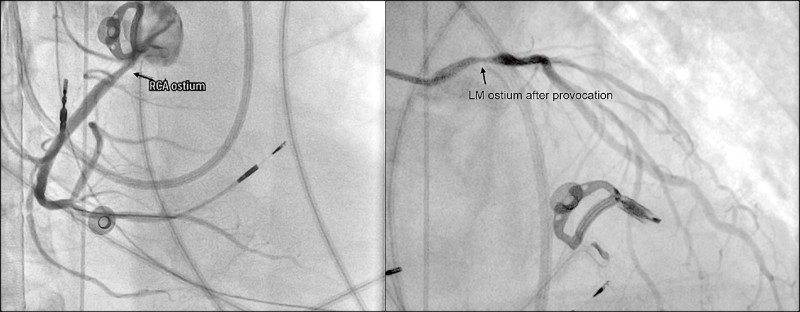

59歲洪先生有長期菸癮,去年曾2度到院前心肺功能停止(OHCA),後續疑似房室傳導阻滯,裝置心臟節律器出院,不料近期心跳驟停再度OHCA送醫,半年內4度心跳驟停瀕死,經啟動葉克膜救回一命,最終找出他罹患罕見嚴重的「雙側冠狀動脈痙攣」,造成冠脈劇烈收縮、血流瞬間減少甚至中斷,進而誘發致命心律不整與心跳停止。

心臟功能室主任葉冠宏指出,常見的冠狀動脈疾病包括動脈硬化與血管阻塞,而冠狀動脈痙攣則是血管抽筋,為血管突然且劇烈收縮,使血流瞬間減少甚至中斷,可能引發嚴重心律不整,甚至導致心跳停止。

他說,臨床觀察顯示,冠狀動脈痙攣與多重因素相關,包括高血壓、高血脂、糖尿病等三高族群風險較高,同時與自律神經失衡有關,尤其是交感神經過度活化,容易造成血管異常收縮,部分病人在發作前可能出現胸悶、胸痛、心悸或冒冷汗等症狀,也有人一發作,馬上併發嚴重心律不整,導致猝死,因而需透過病史、心電圖變化、冠狀動脈攝影或心導管,進行誘發測試等檢查綜合判斷,及早發現並介入治療,才能降低致命風險。